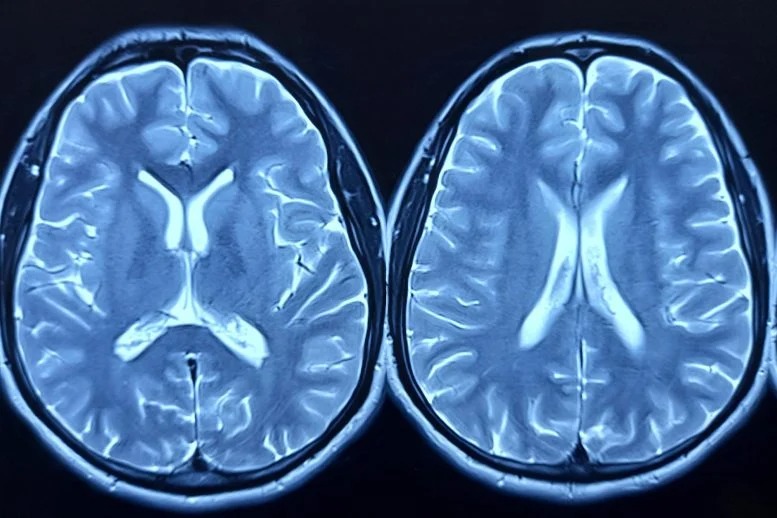

En lo que se considera el estudio más grande de su tipo utilizando tejido cerebral de donantes afroamericanos, científicos de la Universidad de Boston identificaron numerosos genes cuyos niveles de actividad diferían entre casos de Alzheimer y controles. Muchos de estos genes no habían sido vinculados previamente con la enfermedad mediante otras investigaciones genéticas. El resultado más sorprendente fue un aumento significativo en la expresión del gen llamado ADAMTS2 en el tejido cerebral de personas con la enfermedad confirmada por autopsia.

Para realizar este análisis, el equipo recolectó muestras de la corteza prefrontal post-mortem de doscientos siete donantes afroamericanos a través de diversos centros de investigación financiados por el gobierno. El gen ADAMTS2 emergió como el más alterado y también ocupó el primer lugar en un estudio separado que analizó tejido cerebral de una cohorte mucho más grande de ascendencia europea. En dicho trabajo previo, se comparó la expresión genética entre personas con síntomas cognitivos y aquellas que permanecieron resilientes a pesar de tener patología cerebral.